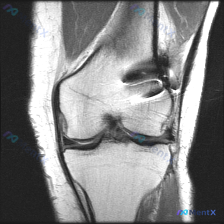

这是一份膝关节MRI T2序列冠状位影像,核心疑问是「观察到Meniscal abnormality(半月板异常)」,我们来一步步拆解分析。

- 半月板:内外侧半月板体部都是正常三角形低信号,形态完整,没有延伸到关节面的高信号撕裂线,也没有半月板内部弥漫性高信号的变性改变——半月板本身其实是正常的

真正的异常出现在股骨远端外侧髁关节软骨面上方的关节腔内:这里可以看到明显条状低信号影,还伴有局部伪影干扰,出现了磁敏感伪影(局部图像扭曲、信号缺失)。

这种强低信号伴磁敏感伪影,是典型的金属异物/金属植入物的影像学表现,条状形态提示是关节内金属内固定物,比如缝合锚钉、金属螺钉这类手术植入物。

初始判断的「半月板异常」是误判,真正的异常是金属植入物带来的伪影,这是膝关节术后非常常见的影像学表现,位置来看最可能是前交叉韧带重建术后的固定螺钉,或者半月板修复术后的锚钉。

目前影像上没有看到急性损伤的迹象,所有未被伪影遮挡的结构都基本正常,但伪影区域确实存在隐匿性病变无法排除的可能。